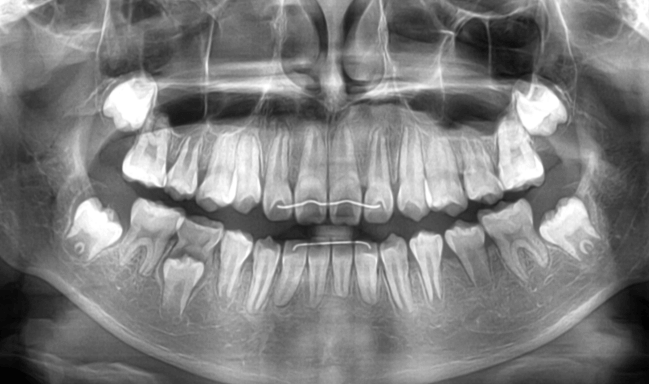

早期矯正治療 埋伏歯症例②

主訴 | 上顎前歯の位置異常に不安を抱え、歯並びと将来的な咬合状態を整える目的で来院された患者様です。 特に左側の前歯(中切歯および側切歯)の萌出が確認できないことがきっかけとなりました。 |

---|---|

診断結果 | 8歳3か月の男児。 左上1番(中切歯)と左上2番(側切歯)が埋伏し、発育方向にも異常が認められました。加えて、一部先天性欠如も確認されており、歯列全体の成長に影響を及ぼす可能性があると診断されました。 |

治療内容 |

|

治療後の経過 | 動的治療後は3〜4か月ごとの定期検診を行い、上下顎の骨の成長や第二大臼歯の萌出状況を確認しながら、本格的な矯正治療を行う |

治療期間 | 動的治療期間:約5年10か月 |

治療費用 | 460,000円(税別) |